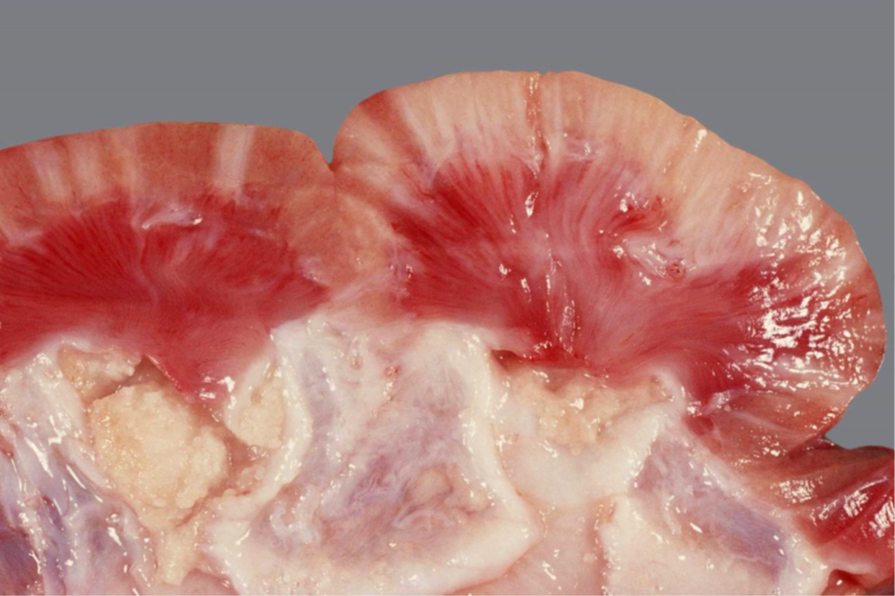

Rind, Niere: Hochgradige chronische diffuse Amyloidose der Niere (Amyloidnephrose)

Beschreibung:

Nierenrinde hellbeige

Oberflächefeingranuliert, speckig

die Renculi erscheinen prominent

derbe Konsistenz

Hintergrundwissen/ Pathogenese/Ätiologie

- Amyloid ist ein fibrilläres Protein, in dem die β-Faltblattstruktur dominiert vermehrter Anfall durch

gesteigerte Synthese oder unvollständige Proteolyse

- Amyloidnephosen v.a. bei Rind, Hund, Katze

AA Amyloid:

- In der Niere meist reaktive systemische Amyloidose: chronischen Entzündungsprozessen ->

gesteigerte Synthese von Serum-Amyloid-A-Protein (Akute-Phase-Protein) durch Hepatozyten ->

Abgabe ins Blut sekundäre Ablagerung von AA-Amyloid vor allem in den Glomeruli

- Familiäre Amyloidose (z.B. Shar-Pei, Abessinerkatze)

AL-Amyloid:

- Selten, z.B. beim Multiplen Myelom

- Beeinträchtigung der glomerulären Filtration durch vermehrte Durchlässigkeit -> Proteinurie, nephrotisches Syndrom

- Differentialdiagnose: Lymphom